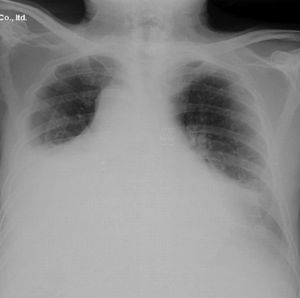

Subsequently, echocardiography showed: left ventricular hypertrophy, with conserved size and systolic function, mild mitral and aortic insufficiency, with the rest of the valves normal, slight pulmonary hypertension and moderate anterior pericardial effusion and moderate to severe posteriorly with fibrin without collapse during dyastole of the right chambers (Fig. 2).